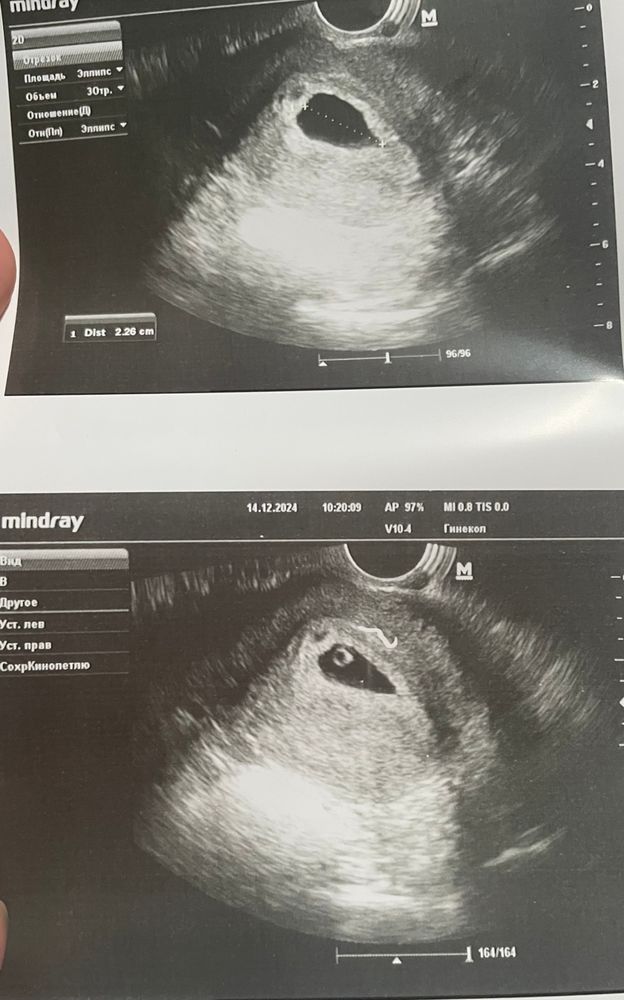

Посмотрите пожалуйста УЗИ 6+2

Кто разбирается ..сегодня была на УЗИ ,чудо женщина узист заявила что желточный мешочек вообще никто не мерит ,потом вообще сказала что Пя 11 мм,оказалось п